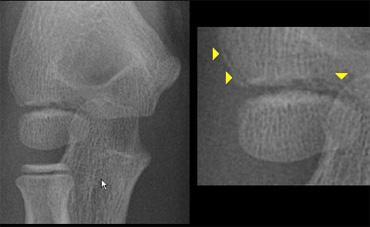

Radial neck fracture with tilt. Notice trochlear ossifications projecting in between humerus and ulna simulating intra-articular fragments.

Điều quan trọng cần nhận biết là bình thường chỏm quay có một góc nghiêng nhất định (lên đến 15°).

The radial epiphysis is slipped (arrows). The radiocapitellar line does not pass through the capitellum indicating dislocation and there is a fracture of the olecranon

Gãy cổ xương quay cũng như trật đầu xương quay trong 50% trường hợp có liên quan đến các tổn thương khuỷu tay khác.

Thường gặp nhất là gãy mỏm khuỷu.

Khi đầu xương quay còn rất nhỏ, trượt đầu xương quay có thể bị bỏ sót (hình).